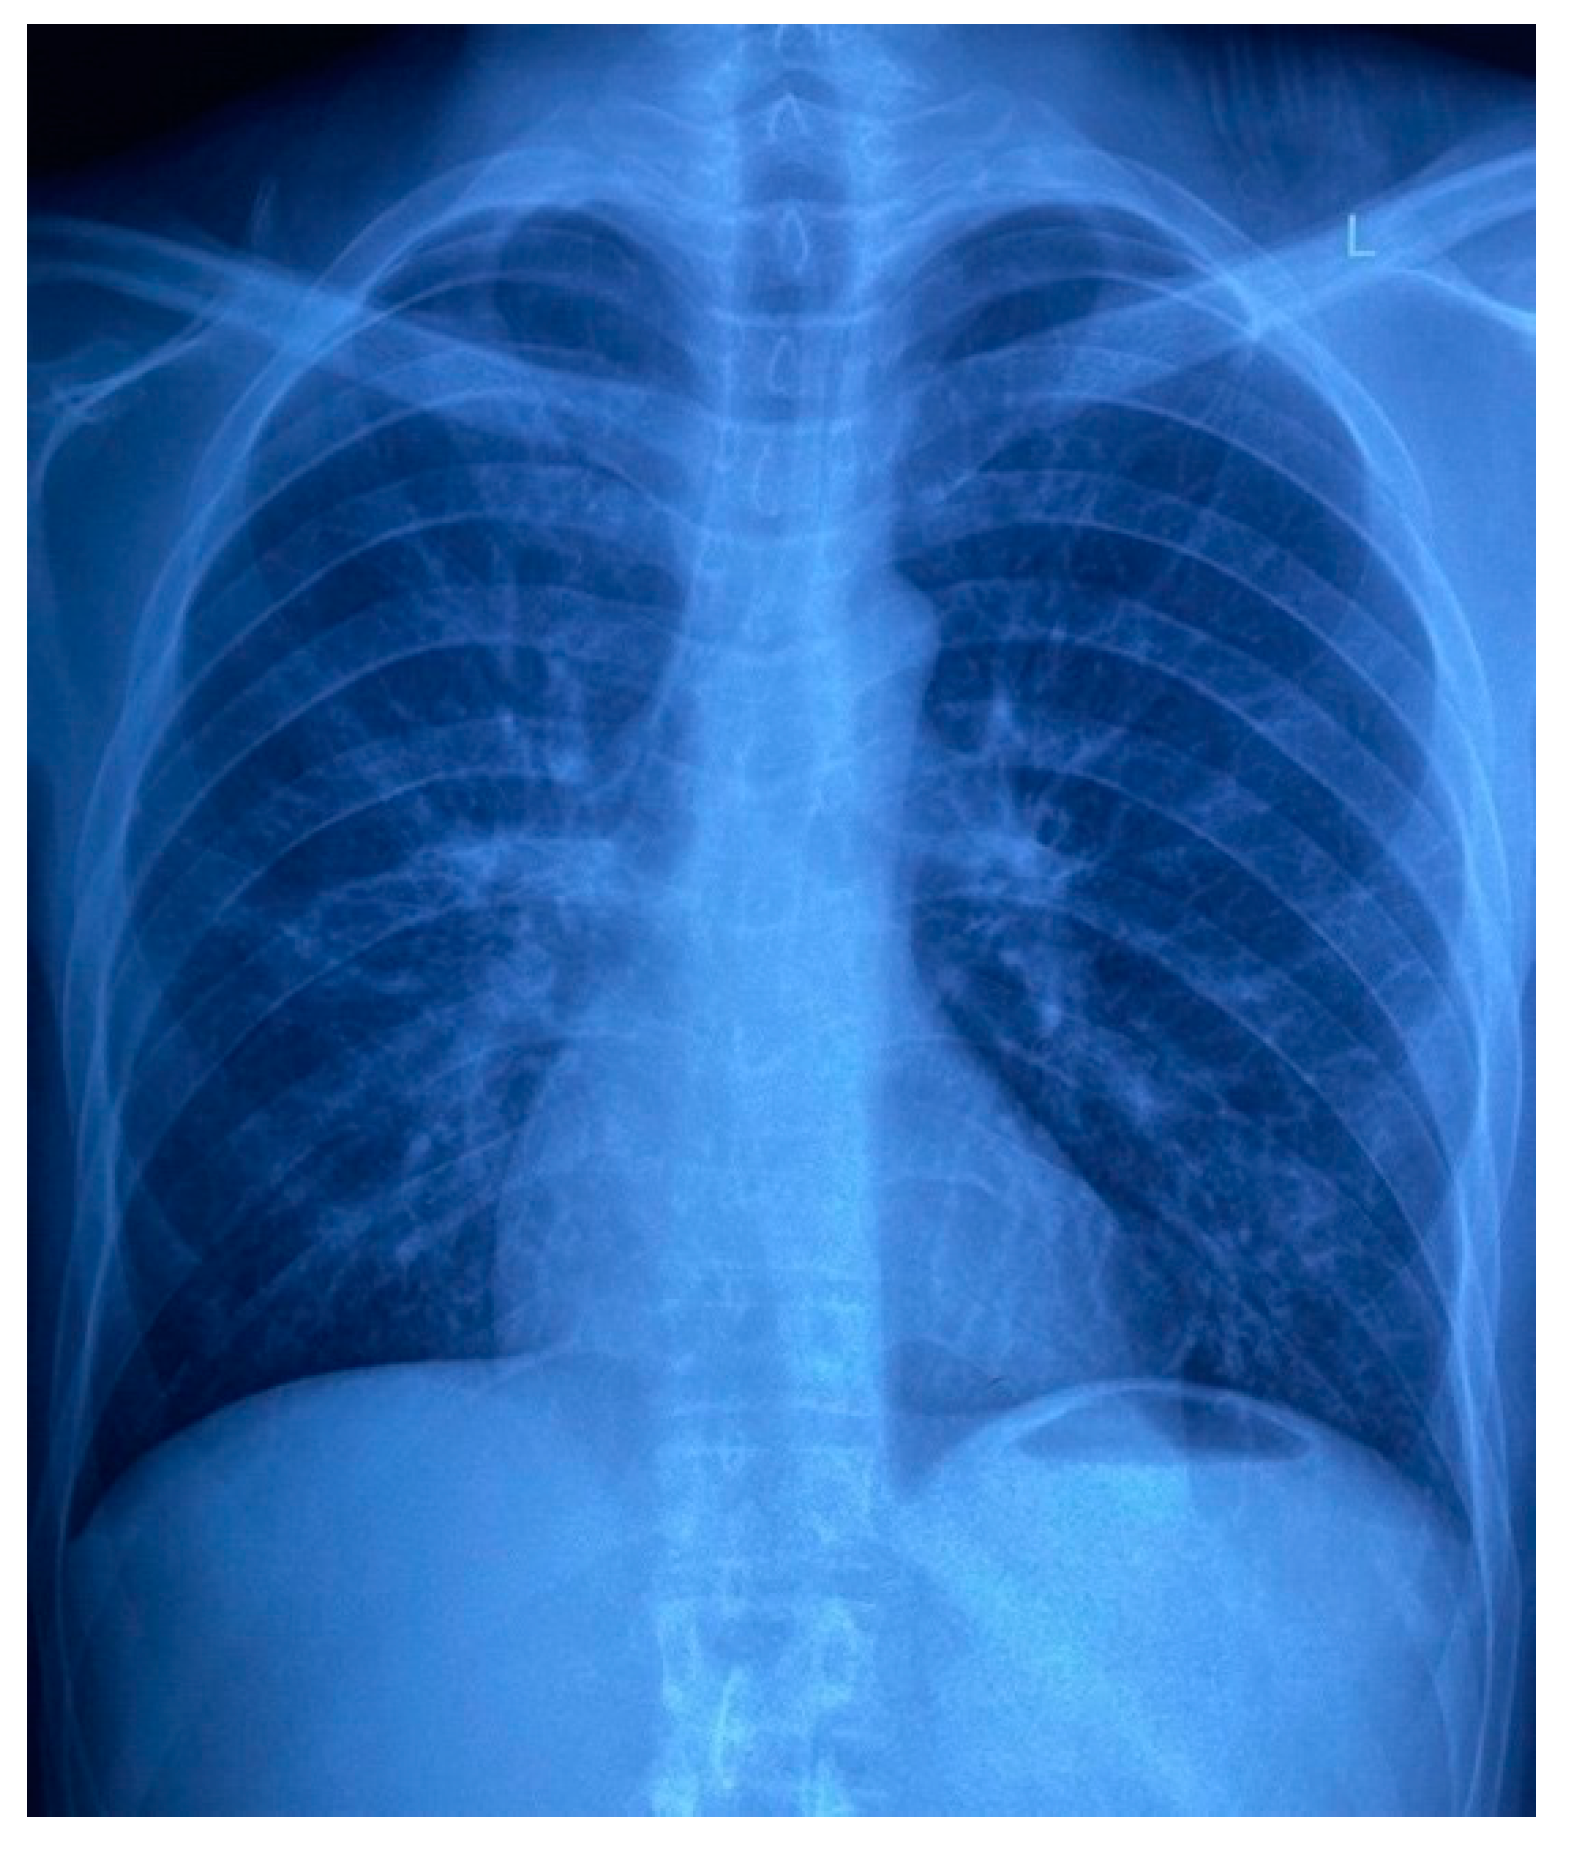

Routine laboratory results on admission showed a normocytic anaemia, lymphopenia, a raised C-reactive protein of 141 mg/L and a normal procalcitonin of 0.09 μg/L. The CD4 cell count was 5 cells/μL and an HIV viral load was 110,000 copies/mL, confirming immunological and virological treatment failure, respectively. Reflex serum cryptococcal antigen screening and a Treponema pallidum antibody test were negative. Contrast-enhanced CT and MRI brain imaging, and cerebrospinal fluid examination did not reveal any abnormalities. A bone marrow aspirate and trephine biopsy excluded an infiltrate, and the anaemia was thought to be secondary to HIV infection. Of note, the admission chest X-ray revealed a nodular infiltrate in the lower lobe and lingula of the left lung (Figure 7) and the X-ray of the patient’s right hand demonstrated a periosteal reaction in the third proximal phalanx and osteolysis of the fifth proximal interphalangeal joint (Figure 8), which suggested a systemic process with multiorgan involvement.

Figure 7. Patient’s chest X-ray on admission, demonstrating a nodular infiltrate in the lower lobe and lingula of the left lung.